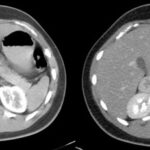

Se presenta el caso de un paciente masculino de 18 años sin antecedentes, que consulta por dolor en hipocondrio derecho de un año de evolución, asociado a palpitaciones, y episodios de HTA. El examen de orina de 24 horas mostró niveles elevados de catecolaminas. En la ecografía abdominopélvica y TAC abdominal, se objetiva una formación de aspecto nodular sólida hipoecoica de contornos bien delimitados, de aproximadamente 43 mm x 39 mm, que no muestra vascularización a la señal Doppler color, asociado a la TC abdomen con contraste EV: masa sólida de 38 mm x 31 mm, reemplazando el parénquima de la glándula suprarrenal derecha que realza de forma ávida y heterogénea en fase arterial a expensas de área central con degeneración necrótica. Se prepara con alfa bloqueador, se realiza adrenalectomía total izquierda laparoscópica. La anatomía patológica evidencia feocromocitoma.

El feocromocitoma es una entidad que afecta a pacientes jóvenes y tiene diversos hallazgos imagenológicos, siendo los más característicos por ecografía como masas grandes sólidas o quísticas con calcificaciones, de bordes bien definidos, dependiente de una glándula suprarrenal, en la TAC suelen ser heterogéneas, frecuente la calcificación, hemorragia y necrosis, con marcado realce tras la administración de contraste. Siendo este el gold standard con el protocolo de lavado suprarrenal se compone de una fase sin contraste, una exploración contrastada con un retraso de 60-90 segundos y una tardía a los 15 minutos con densidad > 10UH.